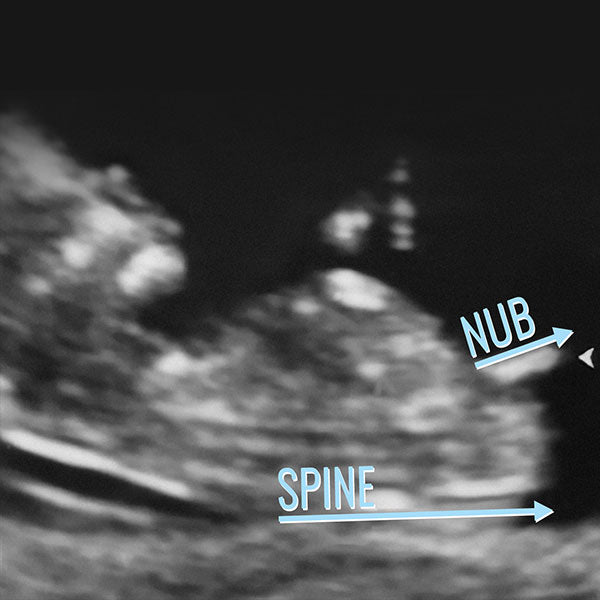

NUB THEORY

To determine gender, The Gender Experts use the following criteria:

- Visibility

- The angle of genital tubercle in relation to the spine

- Shadows and male markers on and surrounding tip of nub

- Shape, including length according to gestational age